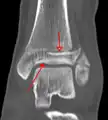

Une fracture triplane de la cheville vue par TDM

CT

Les tomodensitogrammes peuvent être indiqués en cas de risque de fracture fragmentée ou de fracture impliquant la surface articulaire[9]. Cette imagerie peut être utilisée pour la planification chirurgicale.